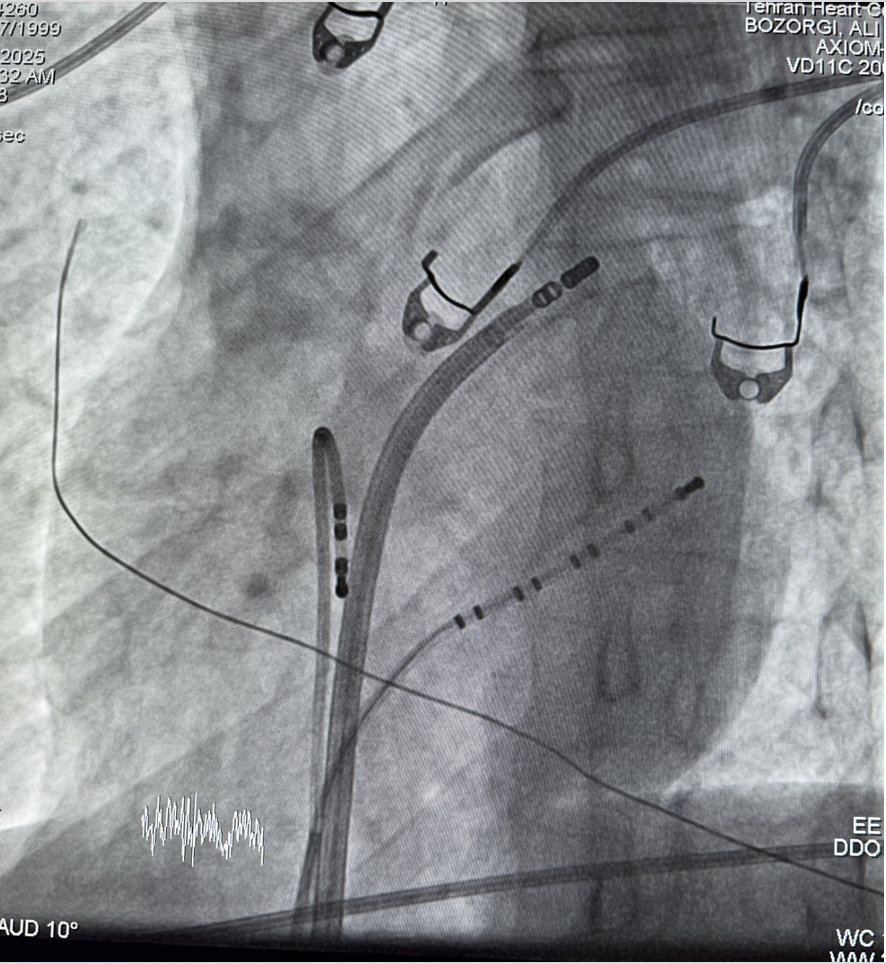

We propose the 5-stage STORM classification for electrical storm – a simple bedside scale that stratifies 30-day mortality from 5% to 50% and helps structure multidisciplinary care